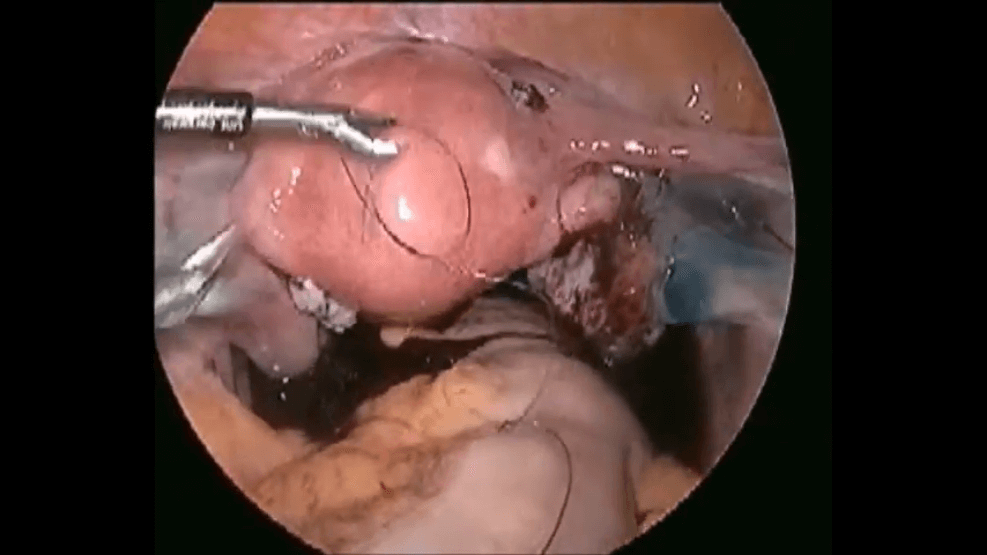

MYOMA SCREW POSITIONS ( External and Internal View) in TLH